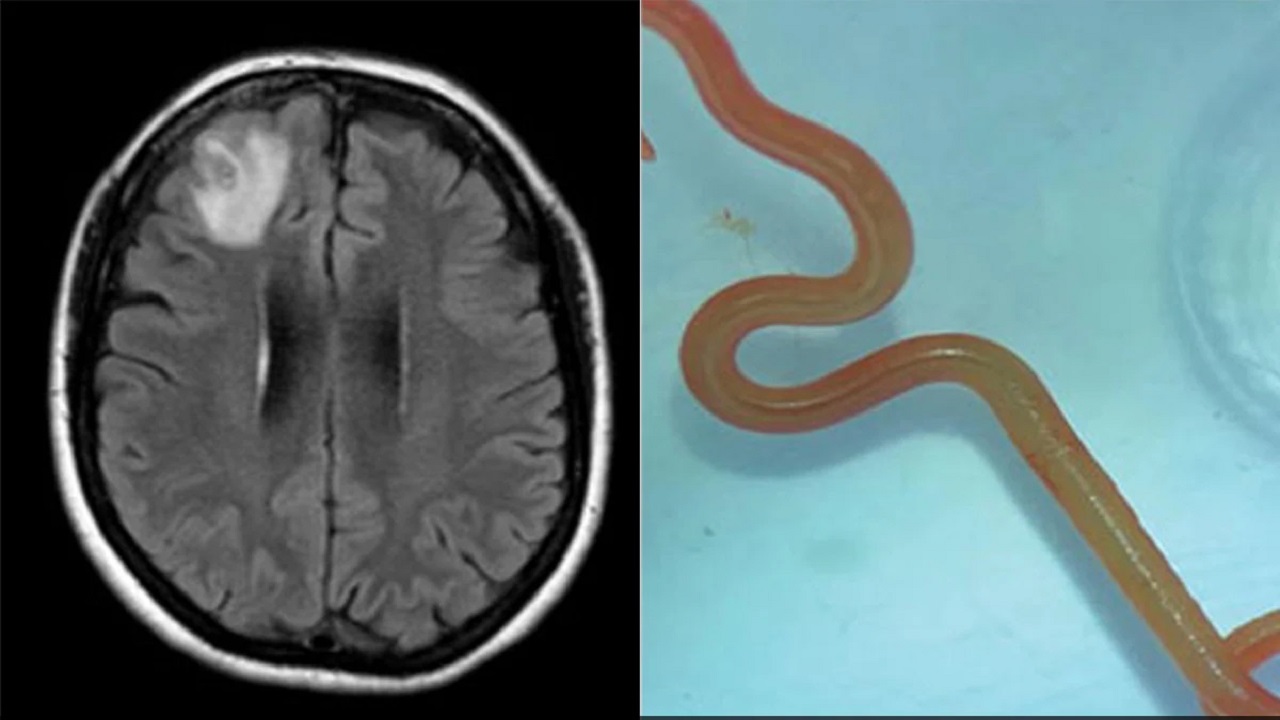

فقد رصد الأطباء من خلال التصوير بالرنين المغناطيسي «آفة ذات شكل غير مألوف» في الجزء الأمامي من دماغ الأسترالية البالغة 64 عاماً كانت تعاني فقدان الذاكرة.

وتبيّن أن هذه الآفة هي عبارة عن دودة من نوع أوفيداسكاريس روبرتسي (Ophidascaris robertsi) الدائرية التي يبلغ طولها ثمانية سنتيمترات، وهي بحسب الباحثين طفيلية تعيش عادةً لدى حيوانات الكنغر والثعابين في أستراليا. وهي تعيش أيضاً لدى حيوانات في مناطق أخرى من العالم، ولكن لم يسبق رصد مثيل لها لدى البشر.

وأتاح اختبار الحمض النووي للأطباء التعرّف على نوع الدودة الطفيلية بعدما ظهر «شكلها الشبيه بالخيط» في الصور الطبية للدماغ.